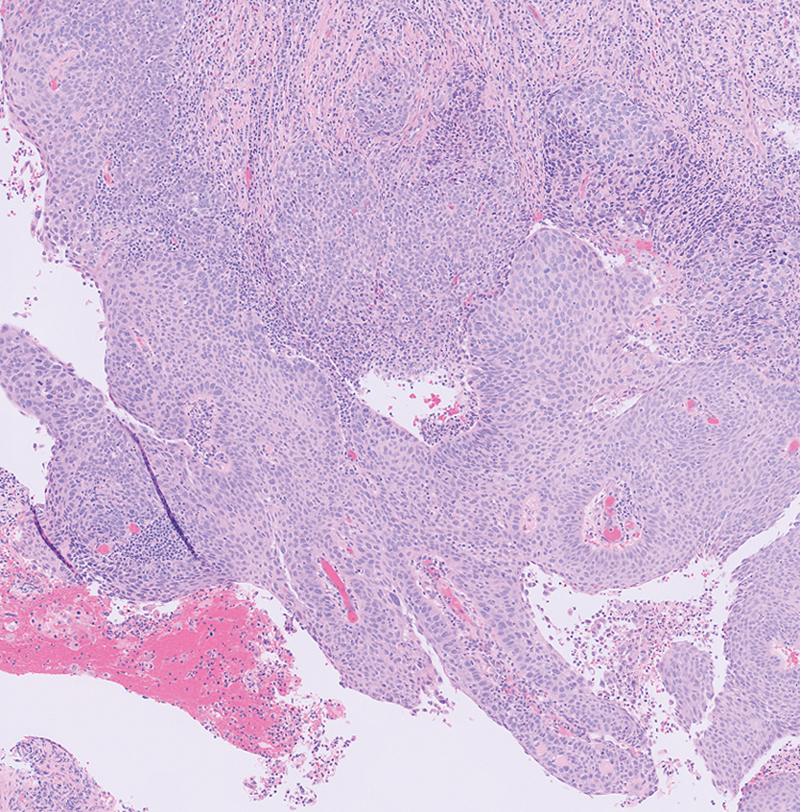

Human papillomavirus (HPV)-associated sinonasal squamous cell carcinoma (SNSCC) (HPV+ SNSCC) is a recently recognized entity that accounts for up to one-third of SNSCC. Although at present these cancers are not routinely tested for HPV, the incidence is increasing and HPV+ SNSCC is associated with superior survival outcomes compared with HPV- SNSCC. Here, we present the case of a patient with HPV+ SNSCC treated with endoscopic resection followed by postoperative radiation and review the literature summarizing epidemiology and management of this disease, with emphasis on the importance of HPV testing in SNSCC.